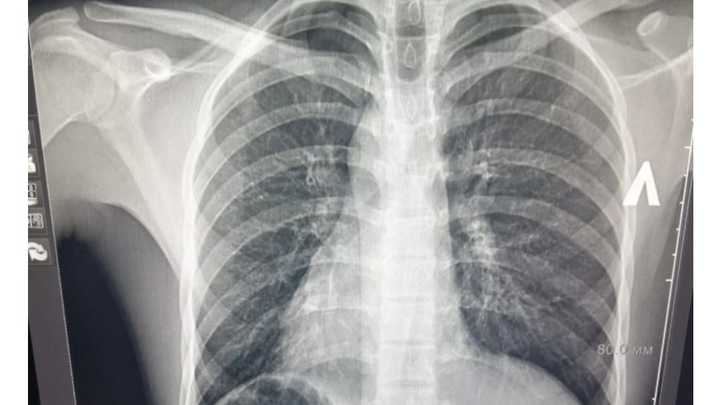

Краснодарские врачи спасли иностранца с зеркальными органами

Фото: скрин с https://bsmp-krd.ru/

Врачи краевой больницы скорой медицинской помощи (БСМП) прооперировали 20-летнего гражданина Таджикистана, у которого все органы расположены зеркально.

Молодой человек поступил в больницу с острыми болями в животе и врачи по симптомам поставили диагноз – воспаление аппендикса. Однако пациент утверждал, что болит с правой стороны. Тогда ему сделали УЗИ, которое подтвердило предварительный диагноз. Однако аппендикс у мужчины, действительно, находился справа. Как и все органы, которые должны были быть с противоположной стороны - сердце, печень, селезёнка и др. Только об этой своей природной уникальности пациент даже не догадывался.